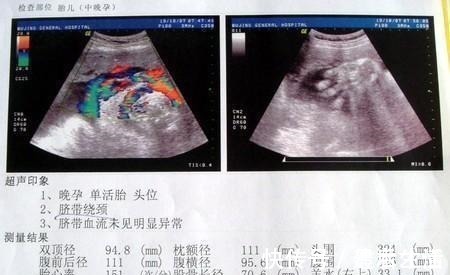

随着时间的推移七个多月后肚子大的像一颗球一样,一开始会是一对双胞胎。直到有一天,陈女士肚子突然整整疼痛,觉得快要生了,于是家人立刻交了救护车将其送到了医院。到了医院后,医生看到这么大的肚子,也断定这是双胞胎跑不了了,于是乎就建议陈女士做剖腹产。与家人商量下同意了。于是,相关手续都处理完毕之后,手术室也准备好了,陈女士被推进了手术室。家人在外静静地等候新的生命诞生。

但是没想到的是当医生划开肚皮后,发现陈女士怀的并不是双胞胎,仅有一个孩子,旁边还有一个跟孩子大小相差不大的子宫肌瘤。医生很小心得将孩子取出来之后,立刻通知相关的医生过来进行切除,还在没有任何生命危险,最后母子平安。医生询问问陈女士为什么肚子里这么大一颗瘤都没有发现?陈女士有些不好意思,原来自己已经生活一胎了,觉得很有经验,所以后来一些检查都没有去做。